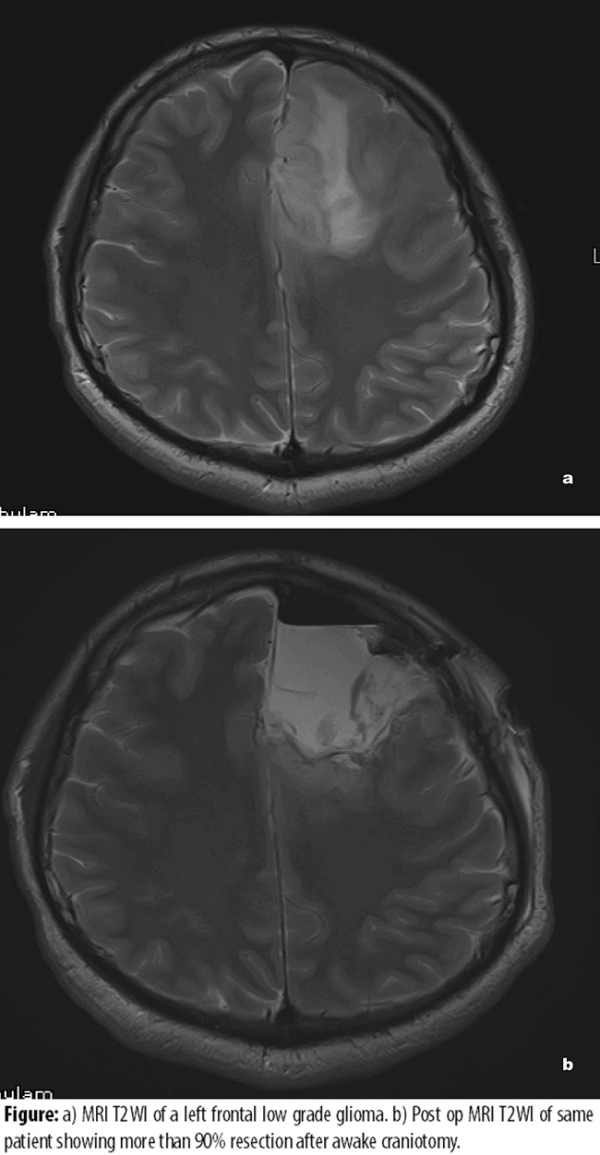

低度神经胶质瘤(LGG)是一组生长缓慢的胶质瘤,但这些肿瘤不经治疗较终也会经历恶性转化并转变为结果较差的高级别肿瘤,甚至恶化为癌症。低度神经胶质瘤是浸润性的,通常位于雄辩的皮层中,并且在大体检查时难以与正常的脑组织区分开,这导致无法完全切除这些病变的固有困难。IDH1突变状态和1p / 19q共缺失的使用的介绍和普及使人们能够更好地了解这些肿瘤的行为,并评估其恶性潜能。早期手术与观察,以及顺利切除的范围是针对这些肿瘤的广泛研究的问题。在过去的三十年中,为数不多的研究试图针对神经胶质瘤家族的这一子集解决这些问题。神经辅助手术,清醒开颅手术,术中电生理监测,术中MRI(iMRI),功能性MRI(fMRI)和纤维束成像等手术辅助设备如今在顺利性更好地切除甚至在雄辩的皮层中起着重要的作用。

1993年,Philippon等人发表了对他们的经验的回顾性分析,并记录了总切除率(GTR)为80%的5年生存率和总切除率(STR)为50%。 Van Weelen等人,在1998年发表了他们的容积结果,切除率大于75%的5年生存率为62%,而切除率小于75%的生存率为18%。Smith等人在2008年进一步阐述了切除体积的相关性,指出切除率达到90-99%时5年生存率能达到97%。他们还将增加的恶性无进展生存期(MPFS)与更高的EOR相关联。在这个大型系列文章中,作者还指出,尽管切除范围广泛,但术前扫描中的大肿瘤与较低的OS,PFS和MPFS相关。同样,McGirt等人在同一年发表了他们的系列文章,显示总切除术(GTR)的95%的5年生存率,近总切除术(NTR)的80%的5年生存率和次全切除术(STR)的70%的生存率,基于术后T2 MRI上残留的FLAIR异常。他们记录了GTR增加的恶性无进展生存期。

大量证据表明,对于低级别胶质瘤来说,前期手术切除而非等待观察是很好的治疗选择,较大水平的顺利切除不仅改变了疾病的自然病史,而且还好转了总生存率以及无恶性进展的生存率。因此,胶质瘤患者应尽早接受外科手术治疗,而非盲目放化疗或一味寄希望于新药和靶向药,如因病变位置深在或周围脑组织结构复杂而被告知“无法手术”,不妨将目光投向国际范围,INC旗下国际神经外科顾问团(WANG)中不乏如德国巴特朗菲教授、加拿大James T. Rutka教授、意大利Concezio Di Rocco教授等擅于治疗高难度脑瘤的神外教授,国内患者如希望获得更佳预后和前沿治疗方案,可拨打400-029-0925咨询INC国际专家远程咨询以获取其咨询意见,以免贻误治疗良机。